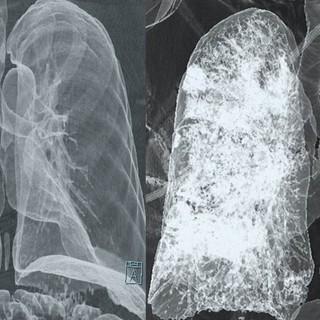

A tüdő CT (komputertomográfia) egy speciális képalkotó vizsgálat, amely részletes keresztmetszeti képeket készít a tüdőről és a környező struktúrákról. Ez a vizsgálat jóval részletesebb képet ad, mint egy hagyományos mellkasi röntgen, így pontosabb diagnózist tesz lehetővé számos tüdőbetegség esetén.

A mellkasröntgen egyszerűbb és gyorsabb vizsgálat, de kevésbé részletes. A CT sokkal részletesebb képet ad a tüdő szerkezetéről, így apróbb eltérések (pl. kis daganatok, gócok) is észlelhetők.